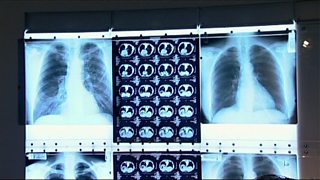

Health experts are tackling an increase in highly infectious drug-resistant TB in London.